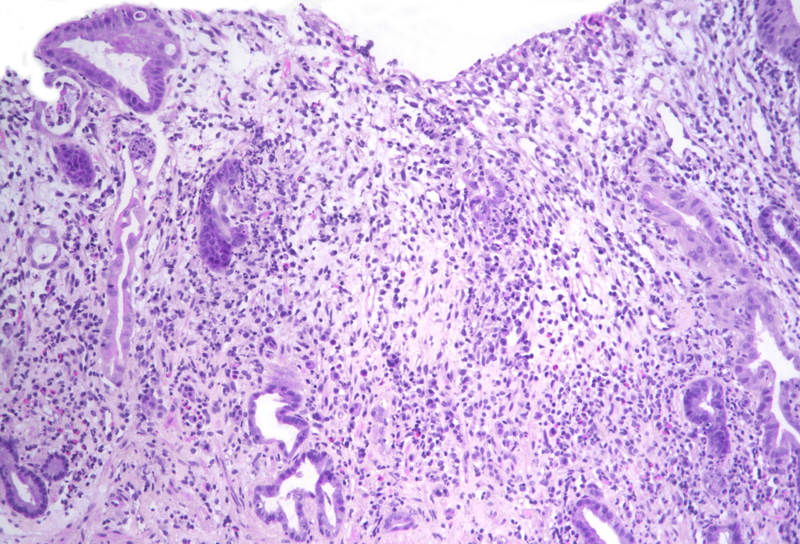

Histology showed an extremely altered gastric mucosa, with architectural distortion by glandular atrophy, degenerative epithelial changes, erosions and an expanded oedematous lamina propria (PANEL A-C). On higher magnification, the lamina propria contained a mixed inflammatory infiltrate, characterized by lymphocytes, plasma cells, eosinophils and neutrophils, focally with abscess formation. We observed withering glands lined by flattened eosinophilic epithelium, occasionally containing apoptotic debris (PANEL D-E); in other areas, little atrophic neuroendocrine nests were found (PANEL F). In summary, there was a severe acute inflammation and signs of acute epithelial injury highly suggestive of a drug-induced gastritis, consistent with injury due to pembrolizumab.